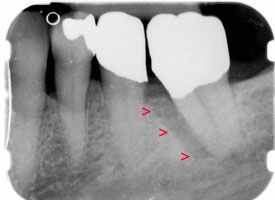

> vorher

Auf dem Röntgenbild sieht man an der Vorderfläche des Zahnes einen tiefen Knochendefekt bis zur Wurzelspitze des Zahnes.